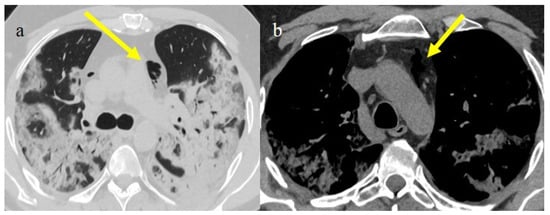

3.3.2. Pneumomediastinum and Pneumothorax

| Typical Appearance | GGOs with a crazy-paving pattern and consolidations in a peripheral and posterior or central-peripheral distribution; multilobar involvement; vascular enlargement, the halo and reversed halo sign; subpleural and parenchymal bands; and architectural distortion. They were predominant since the Delta wave. |

| Atypical Appearance | Lobar consolidation, lung nodules or masses, miliary patterns, tree-in-bud patterns, cavitation, pleural effusion, central distribution, and lymphadenopathy. Atypical appearances were predominant during the Omicron waves. |